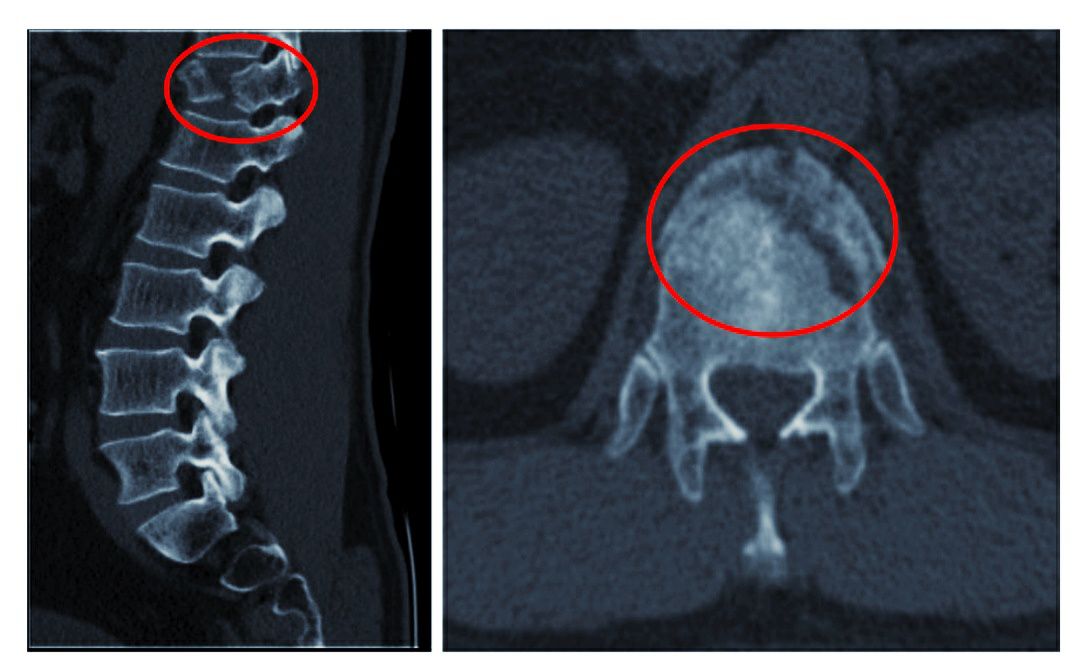

术前胸椎ct失状面三维重建

术前ct:腰4椎体爆裂性骨折.

术后ct示:椎弓根螺钉位置良好,椎体高度恢复正常.